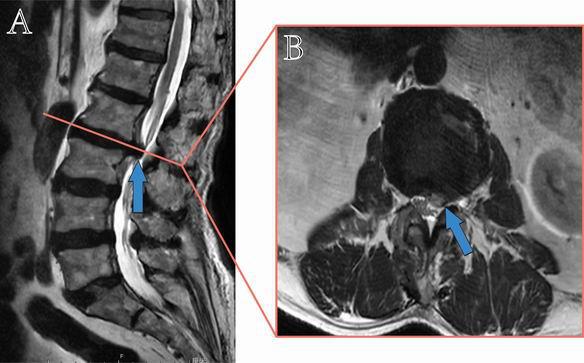

磁共振检查图像(A:矢状位,B:水平位,蓝色箭头示腰椎2/3巨大椎间盘脱出)

缪老伯被诊断为“腰椎2/3巨大椎间盘脱出”,金山医院脊柱外科的熊敏和赵明东医生介绍,这是一种常见于老年人的退化性疾病,往往由年龄衰老椎间盘老化,导致该处纤维环韧带松弛,髓核就会脱出,压迫到旁边的神经根,引起腰腿部剧烈的疼痛、麻木,导致下肢功能障碍。